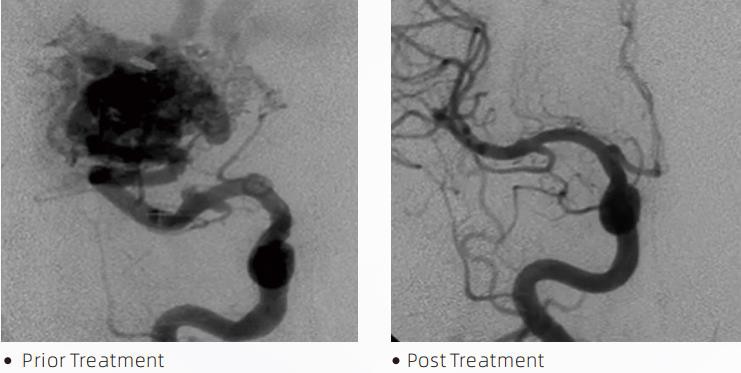

dung nhamTMHệ thống thuyên tắc chất lỏng là một liệu pháp nội mạch can thiệp để điều trị dị tật mạch máu não. Dị tật mạch máu não là một nhóm các bất thường về thần kinh mạch máu lành tính hoặc ác tính có thể dẫn đến xuất huyết nội sọ, nhồi máu não, thiếu máu não và các bệnh khác. Hệ thống thuyên tắc chất lỏng là một thiết bị y tế được sử dụng thông qua việc đưa vào mạch máu đơn giản, làm tắc mạch các mạch máu não bất thường bằng cách tiêm một chất lỏng đặc biệt. Chất lỏng tạo thành sự tắc mạch mô có kiểm soát trong mạch máu, có thể làm giảm tác động của dị tật mạch máu não đối với bệnh nhân. Một ống thông vi mô phân phối tương thích DMSO được chỉ định sử dụng trong mạch máu thần kinh được sử dụng để tiếp cận vị trí tắc mạch. Chất làm tắc mạch dạng lỏng dung nham là một hệ thống chất làm tắc mạch dạng lỏng không dính bao gồm chất đồng trùng hợp EVOH (ethylene vinyl Alcohol) hòa tan trong DMSO (dimethyl sulfoxide) và bột tantalum micronized lơ lửng để tạo độ tương phản cho hình ảnh dưới phương pháp soi huỳnh quang. dung nhamTMcó sẵn ở ba công thức sản phẩm, LAVA-12, LAVA-18 và LAVA-34. LAVA-12: Được khuyên dùng khi cho ăn các mạch siêu nhỏ ở xa và qua các máng ăn nhỏ. LAVA-18: Được khuyến nghị khi tiến hành tiêm cuống nuôi dưỡng gần nidus; LAVA-34: Được khuyên dùng để làm tắc nghẽn dòng chảy cao hơn và các thành phần có lỗ rò lớn hơn.